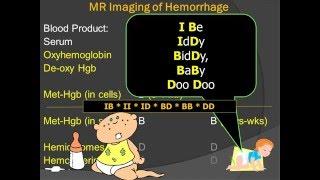

MedPix® Traumatic Brain Injury - Epidural Hematoma: Radiologic-Pathologic Correlation